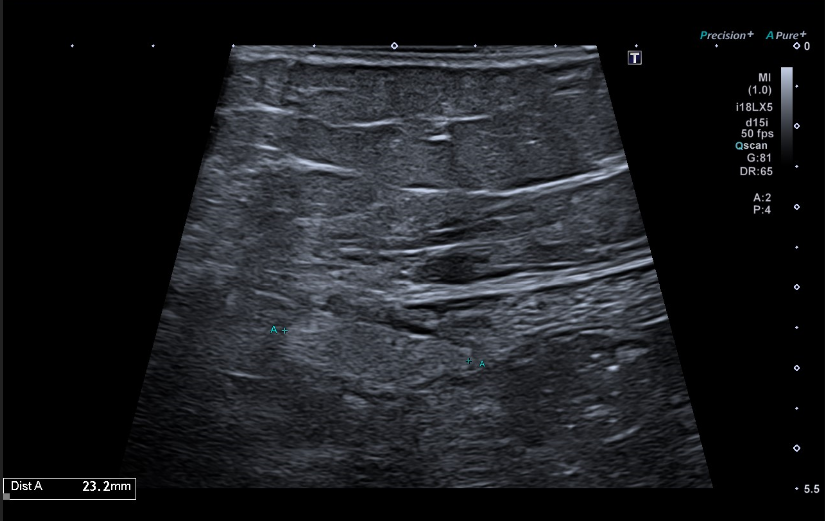

Se realiza una ecografía abdominal en el centro de salud visualizándose una masa hiperecogénica de 15 centímetros, aproximadamente, que parece dependiente del riñón derecho.

Se deriva a la paciente a urgencias hospitalarias donde se realiza una analítica sin objetivarse hallazgos significativos y una nueva ecografía en la que se visualiza una gran formación quística en flanco derecho que impresiona depender del riñón derecho. De manera ambulatoria se realizan un TC toraco-abomino-pélvico y una RMN abdomino-pélvica hallándose una masa abdomino-pélvica derecha de 15 x 13,5 x 12 centímetros de diámetros transversal, craneocaudal y anteroposterior, respectivamente, que impresiona de origen retroperitoneal vs origen ovárico.